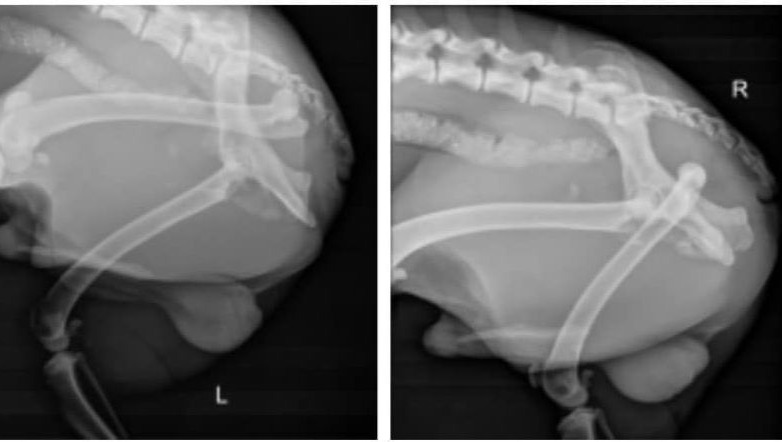

They further stabilized him, took x-rays, and did a few tests.

Then the bad news arrived: He had a fractured pelvis and a broken femur, and the staff recommended emergency FHO (Femoral Head Ostectomy) surgery.

This poor guy was not just hit by a car; he was run over by a car and was left to die in the middle of the desert, without the ability to move and reach food, water or shelter.

He was hospitalized for 24 hours, and then they referred me to a low-cost clinic that was able to perform the surgery at a discounted price of $2,435.